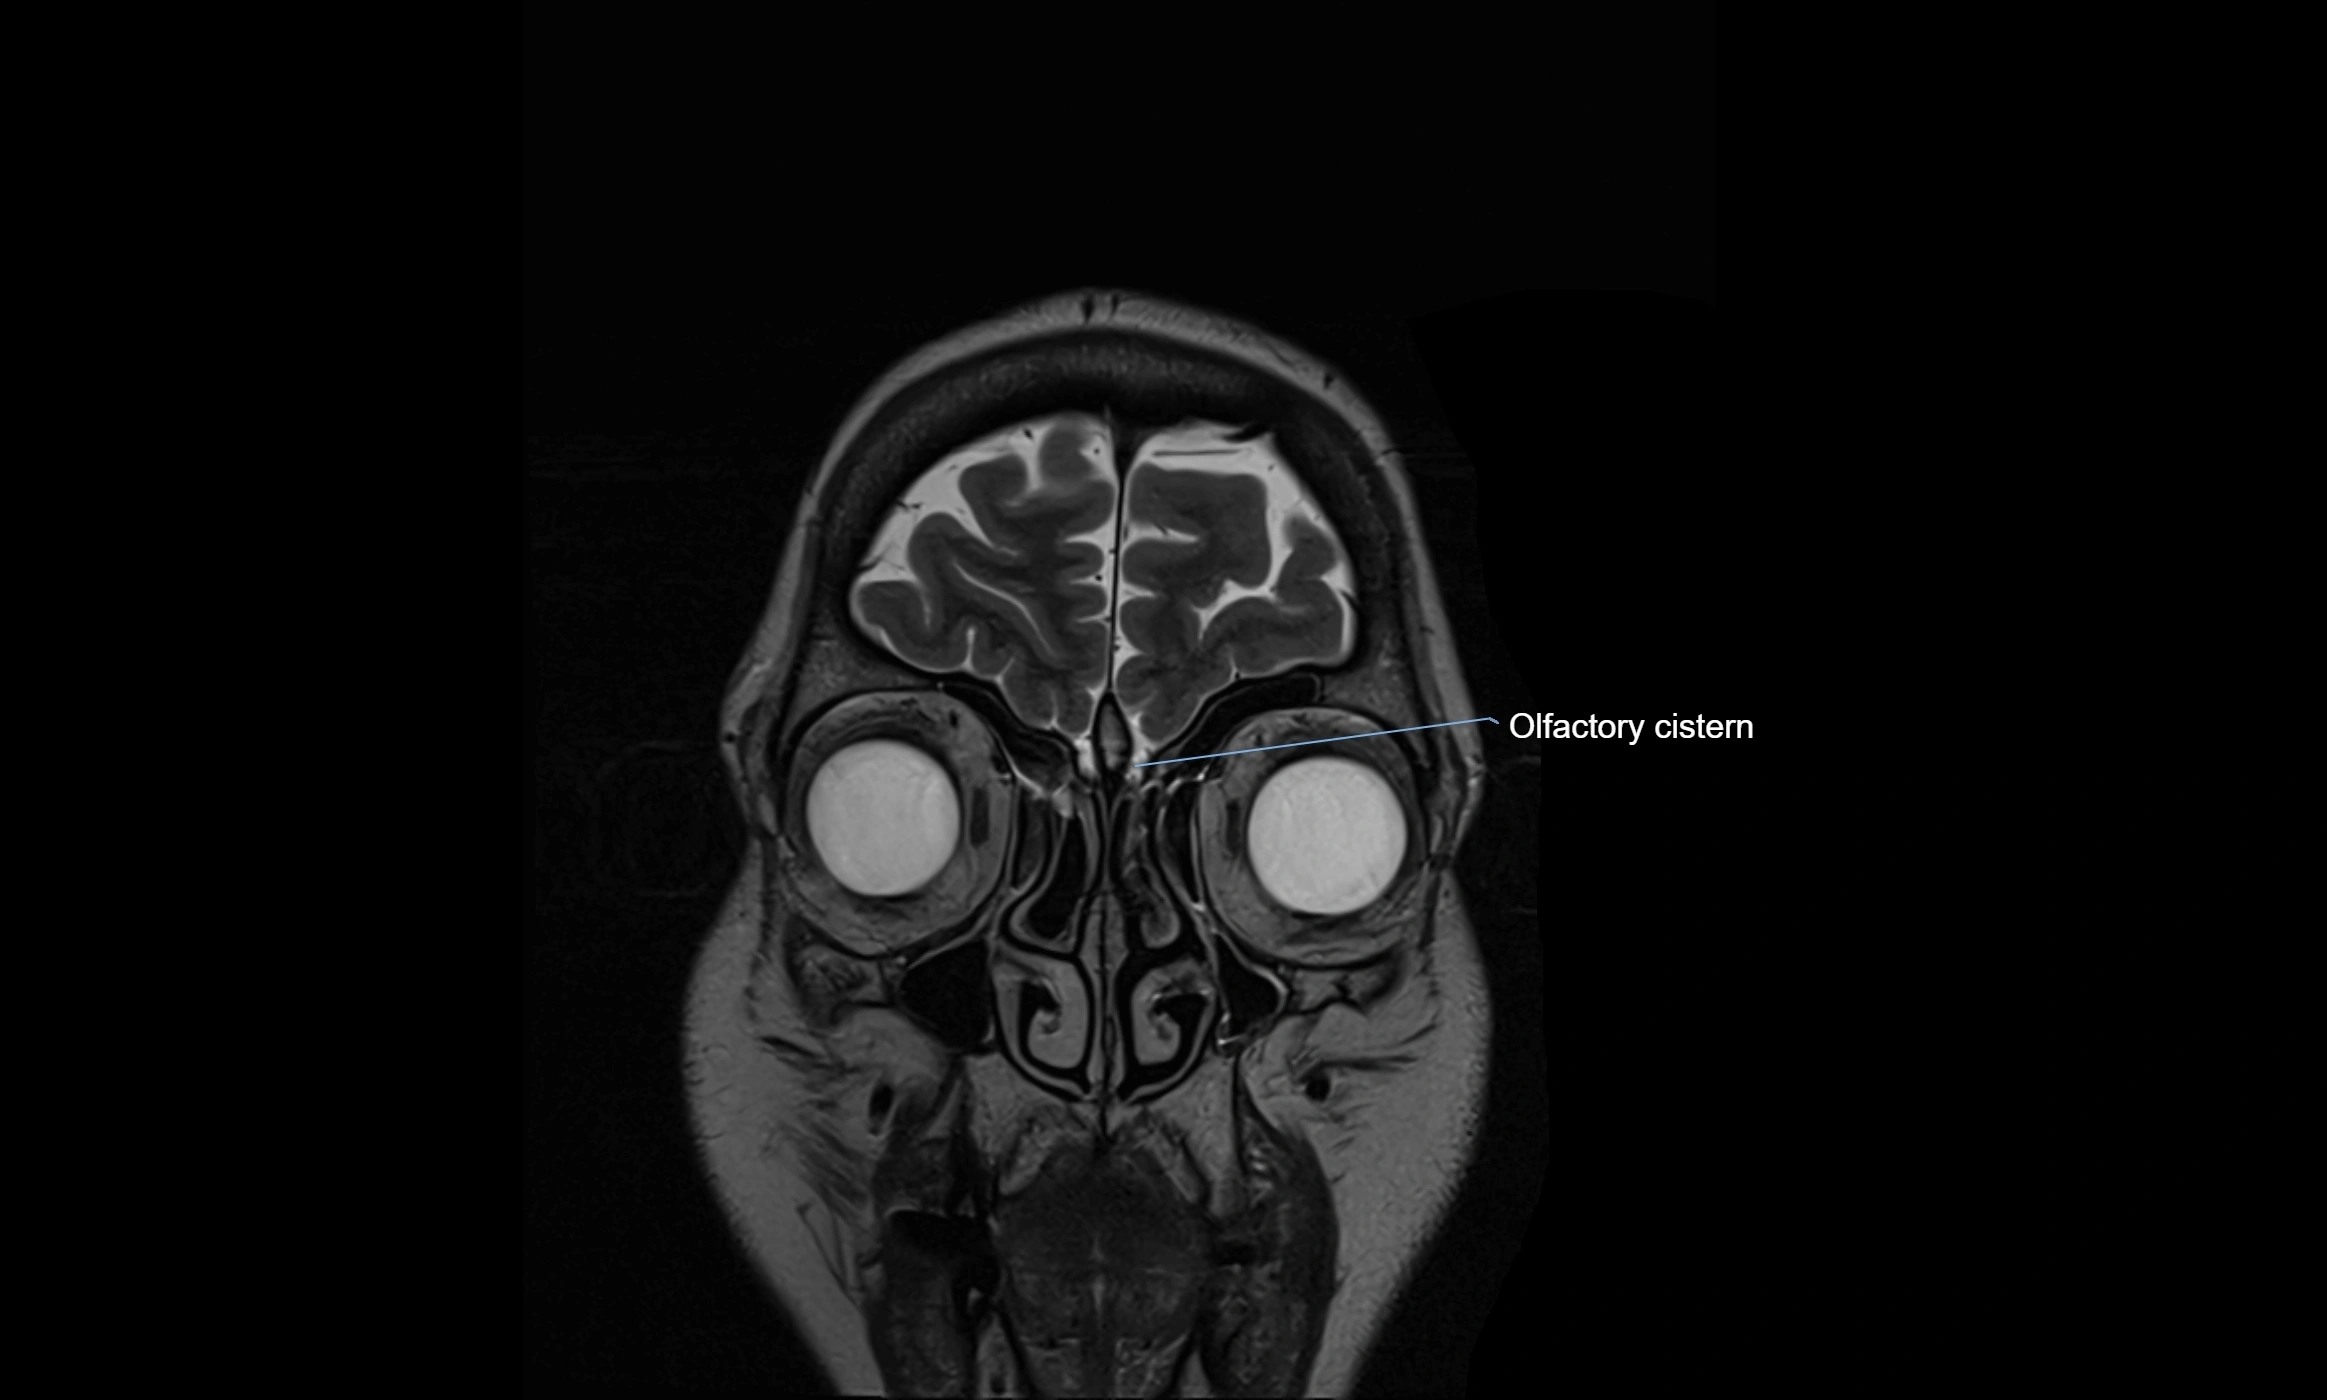

MRI images

image